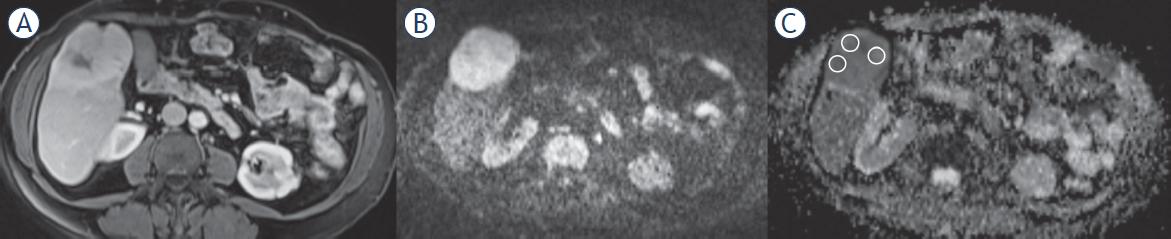

Figure 2

Apparent diffusion coefficient (ADC) values of intrahepatic cholangiocarcinoma (IHCC) and gastrointestinal system (GIS) liver metastases

| Patient Groups | ADC x 10-6mm/sn2 (median, IQR) |

| IHCC | (1293.0), (1422.0–951.75) |

| GIS metastases | (861.0), (1053.0–695.0) |